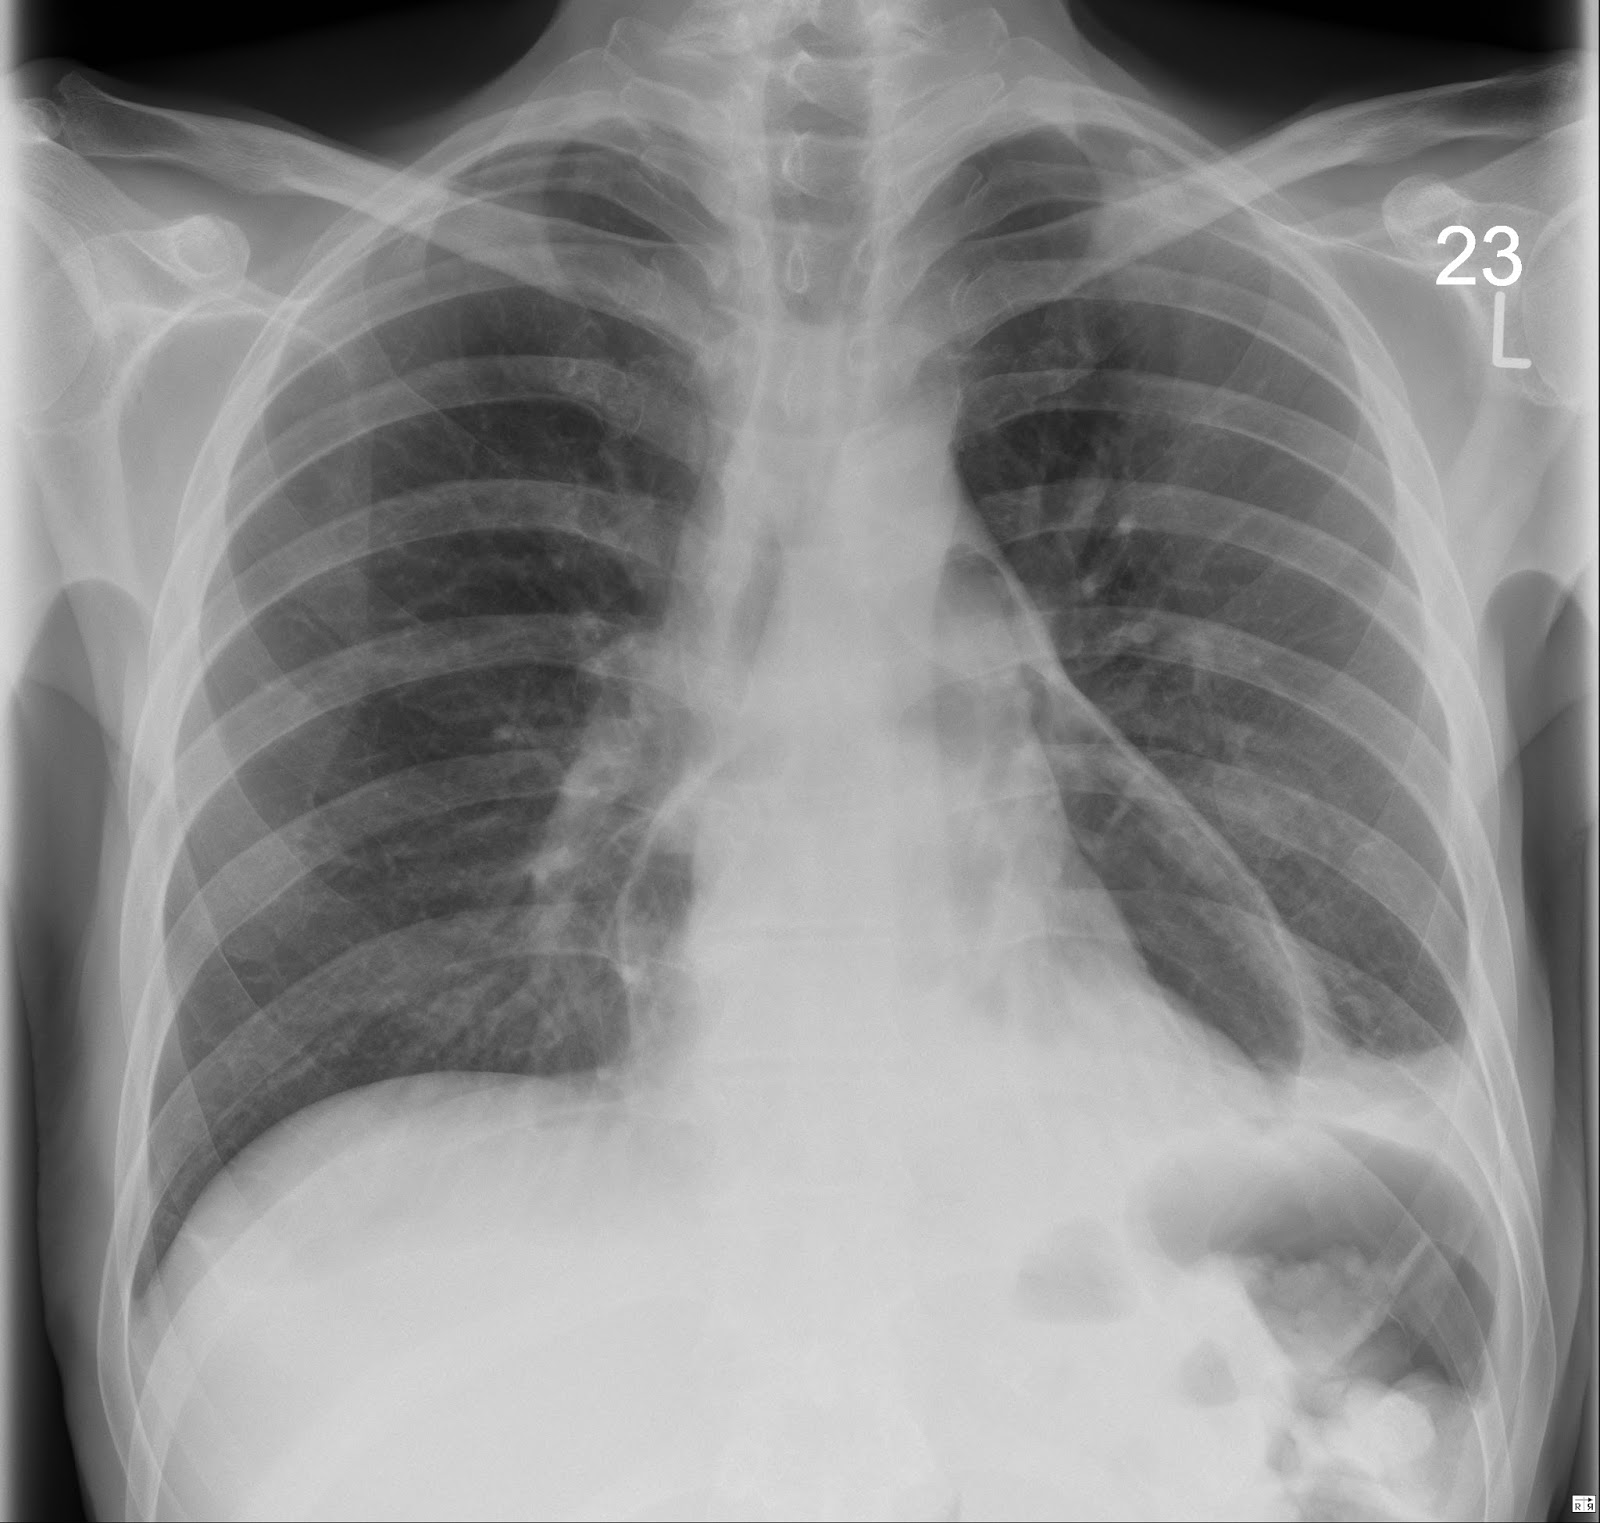

the xray doctor xrayoftheweek 33 previous gastric surgery and now chest pain why?

the xray doctor xrayoftheweek 33 previous gastric surgery and now chest pain why? Chest X Ray Bariatric Surgery Bariatric surgery is increasingly performed to control morbid obesity secondary to failed medical approaches. This surgery reduces the size of your upper stomach to a small pouch about the size of an egg. Sleeve gastrectomy is a bariatric surgical procedure involving resection of the greater curvature of the fundus and body of the stomach to leave approximately 15% of the.. Chest X Ray Bariatric Surgery.